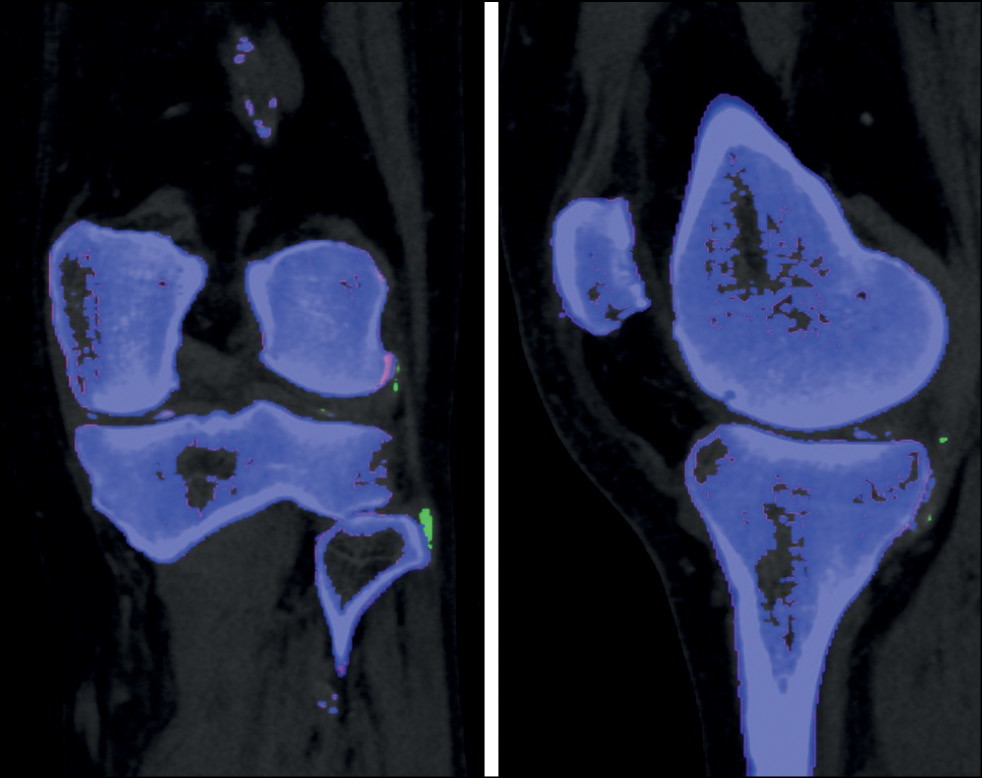

DECT has several configurations: with two perpendicular sources and detectors, with a single source-detector system with quick voltage switching, or with a single X-ray source and a multilayer sandwich detector [26]. Data are processed using three- or two-material decomposition analysis. Two-material decomposition analysis in the diagnosis of gout is performed by uric acid and calcium. Soft tissues are the “reference point” for the algorithm to make judgment concerning the presence of calcium or monosodium urate in the area under study. Thus, a material density (MD) map can be created, on which each component is color coded. In the Siemens DECT systems, cortical bones, cancellous bones, and monosodium urate crystals are coded blue, pink, and green, respectively. Color scales used by other manufacturers’ processing algorithms may differ.

Three-dimensional reconstruction (volume-rendering technique image) with color coding is possible, as are other reconstruction algorithms employed in research (Fig. 2).

Fig. 2. Three-dimensional reconstruction, blended and color-coded image (right ankle joint and small foot joints): blue, pink, and green represent cortical bone, cancellous bone, and monosodium urate crystals, respectively (dual-energy computed tomography findings of the Medical Research and Education Center of the Lomonosov Moscow State University).